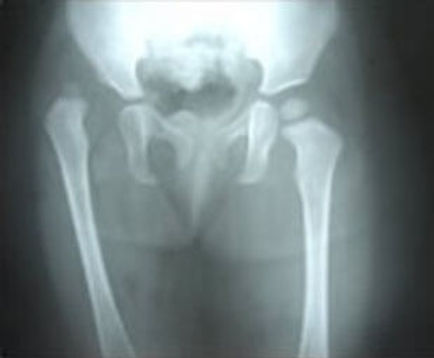

Developmental Dysplasia of Hip

Developmental Dysplasia of the Hip (DDH) is a condition where the hip joint does not develop properly in infants and young children, leading to instability or dislocation. Early diagnosis is crucial for effective treatment, which may include harnessing to secure the hip in the socket, casting, or surgery to correct the alignment and ensure proper joint development. Early intervention is key to preventing long-term complications and ensuring normal hip function.